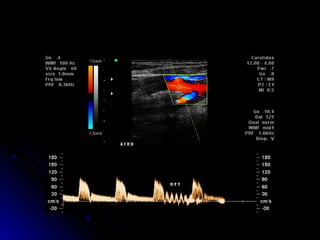

Exame normalExame normal

Paredes arteriais regulares, diâmetros normais,Paredes arteriais regulares, diâmetros normais,

luz anecóide.luz anecóide.

Mapeamento colorido anatômico.Mapeamento colorido anatômico.

Padrão espectral habitual, sem borramentos.Padrão espectral habitual, sem borramentos.

Velocidades sistólicas dentro de faixas normais.Velocidades sistólicas dentro de faixas normais.

ACC, ACI e ACEACC, ACI e ACE

Espectral com VPS e VDEspectral com VPS e VD

Documentar a correção do ângulo DopplerDocumentar a correção do ângulo Doppler